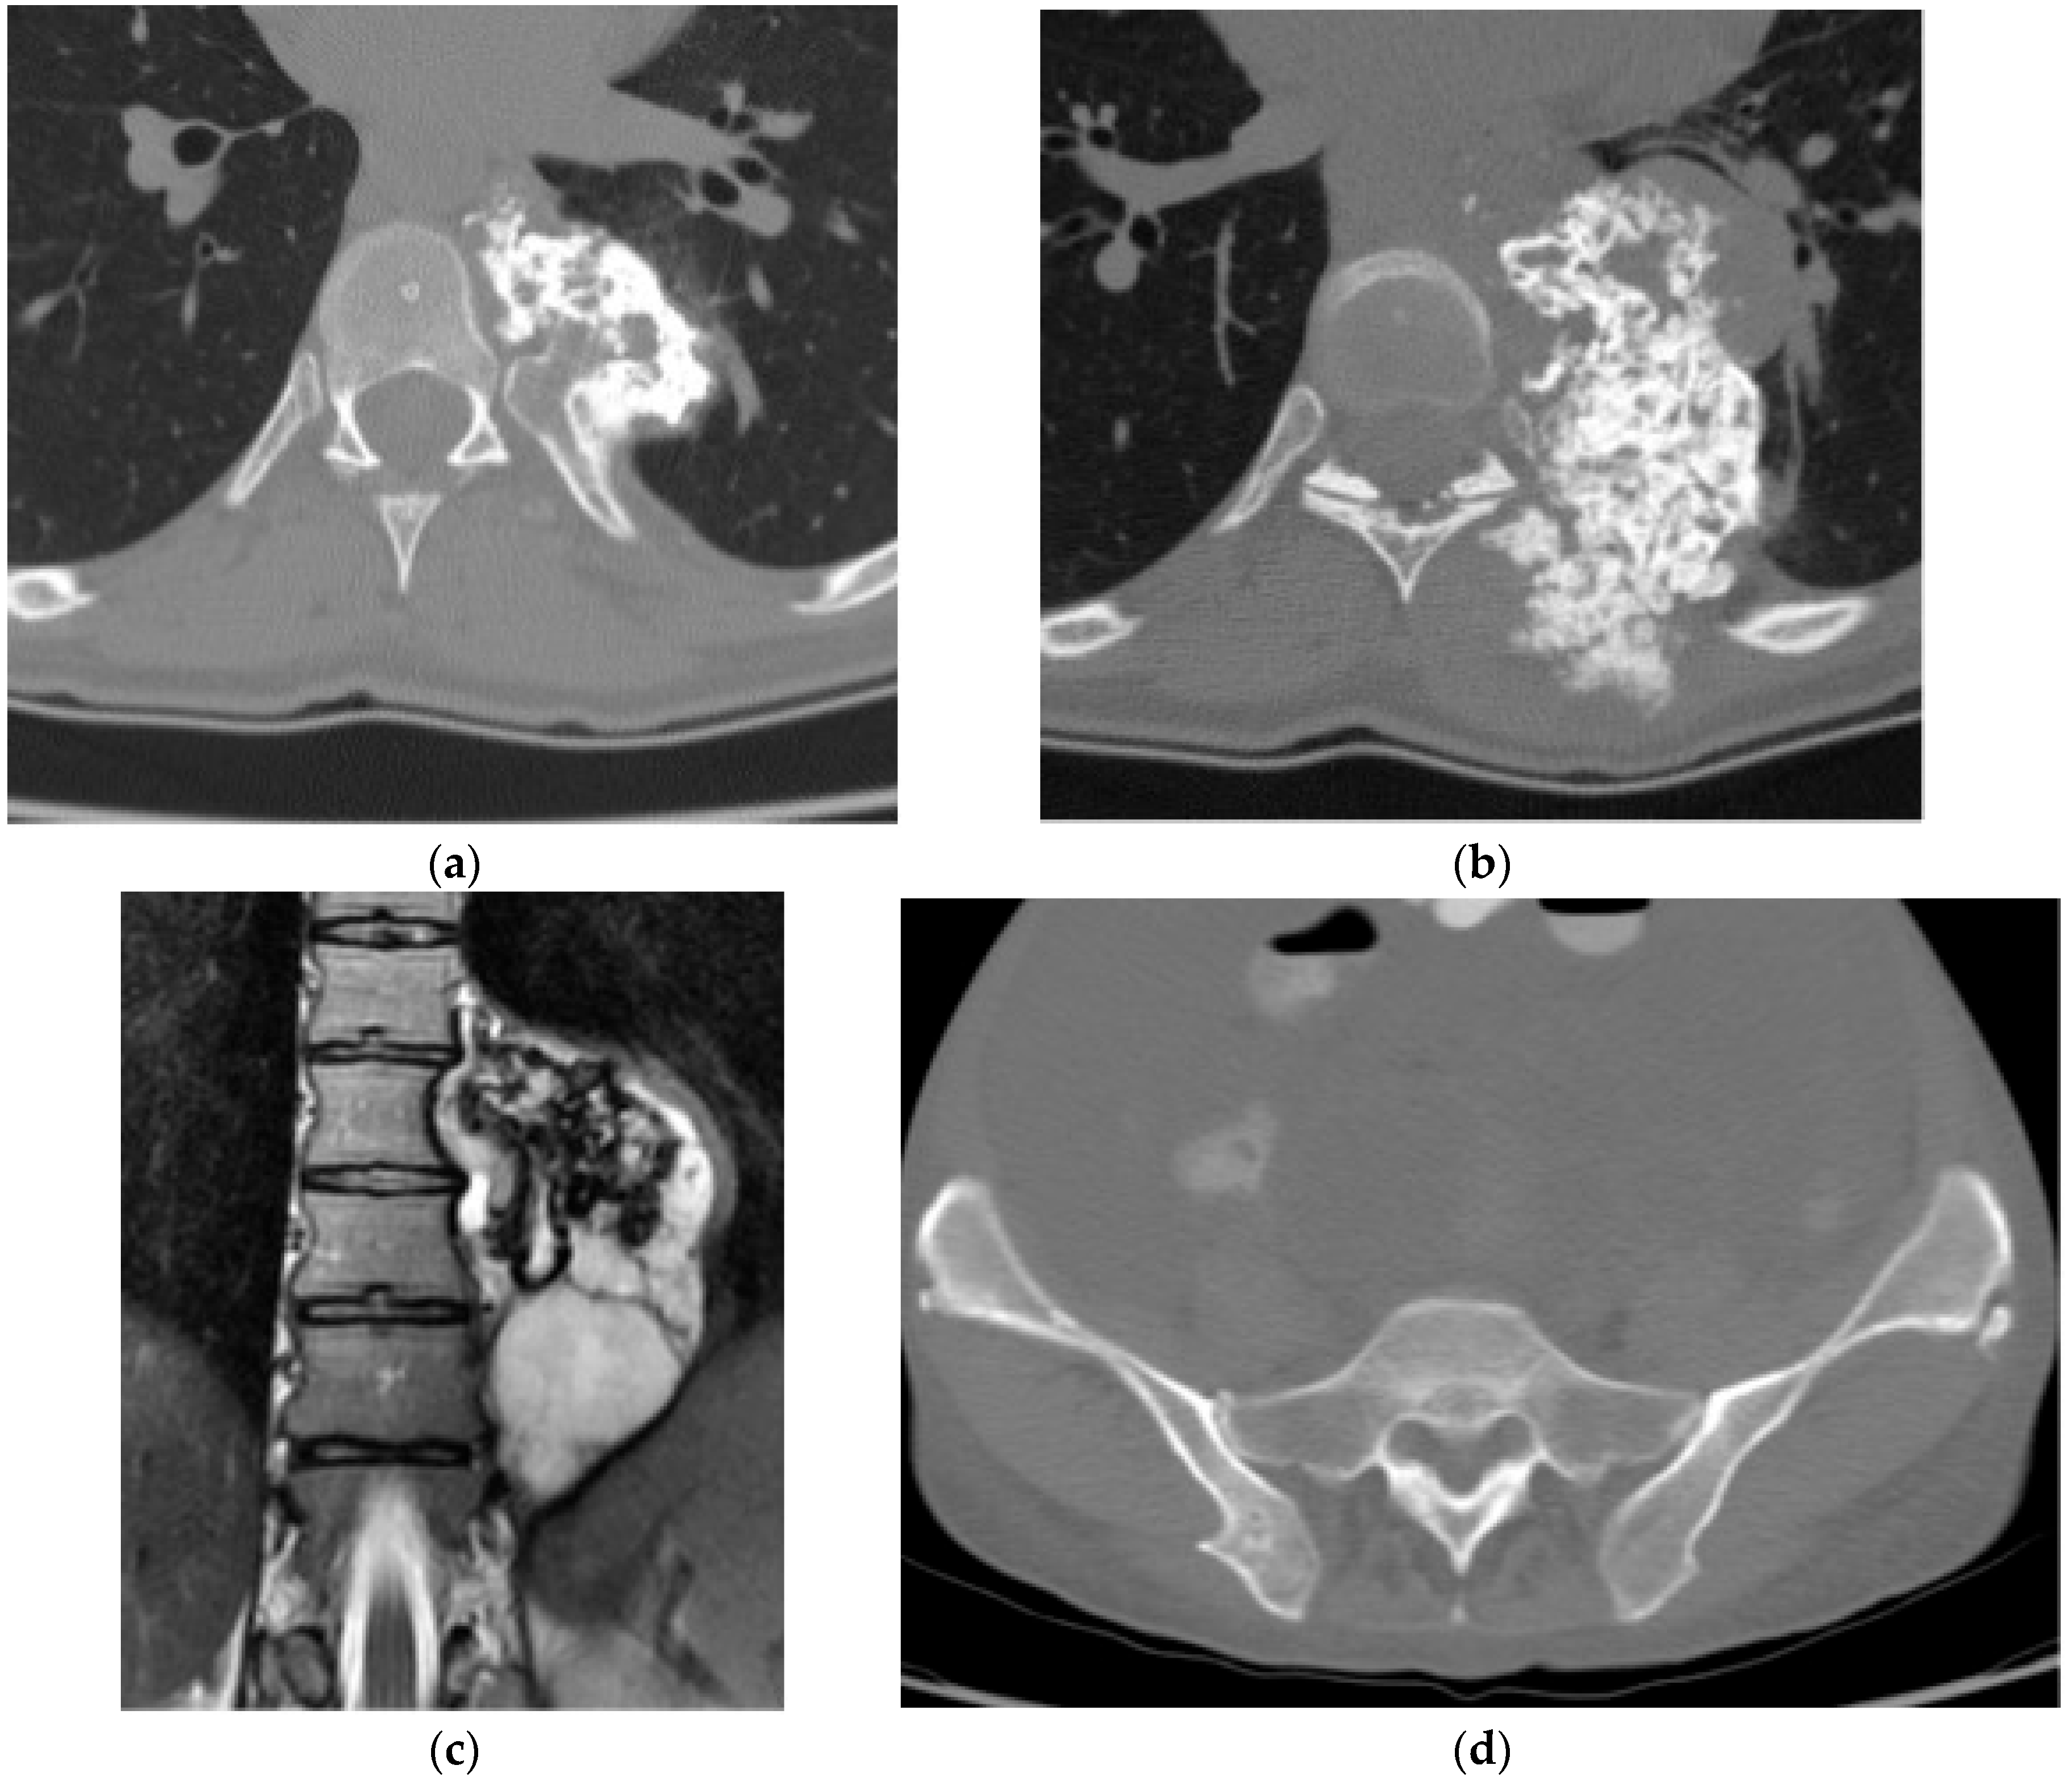

2.1.4. Osteosarcoma